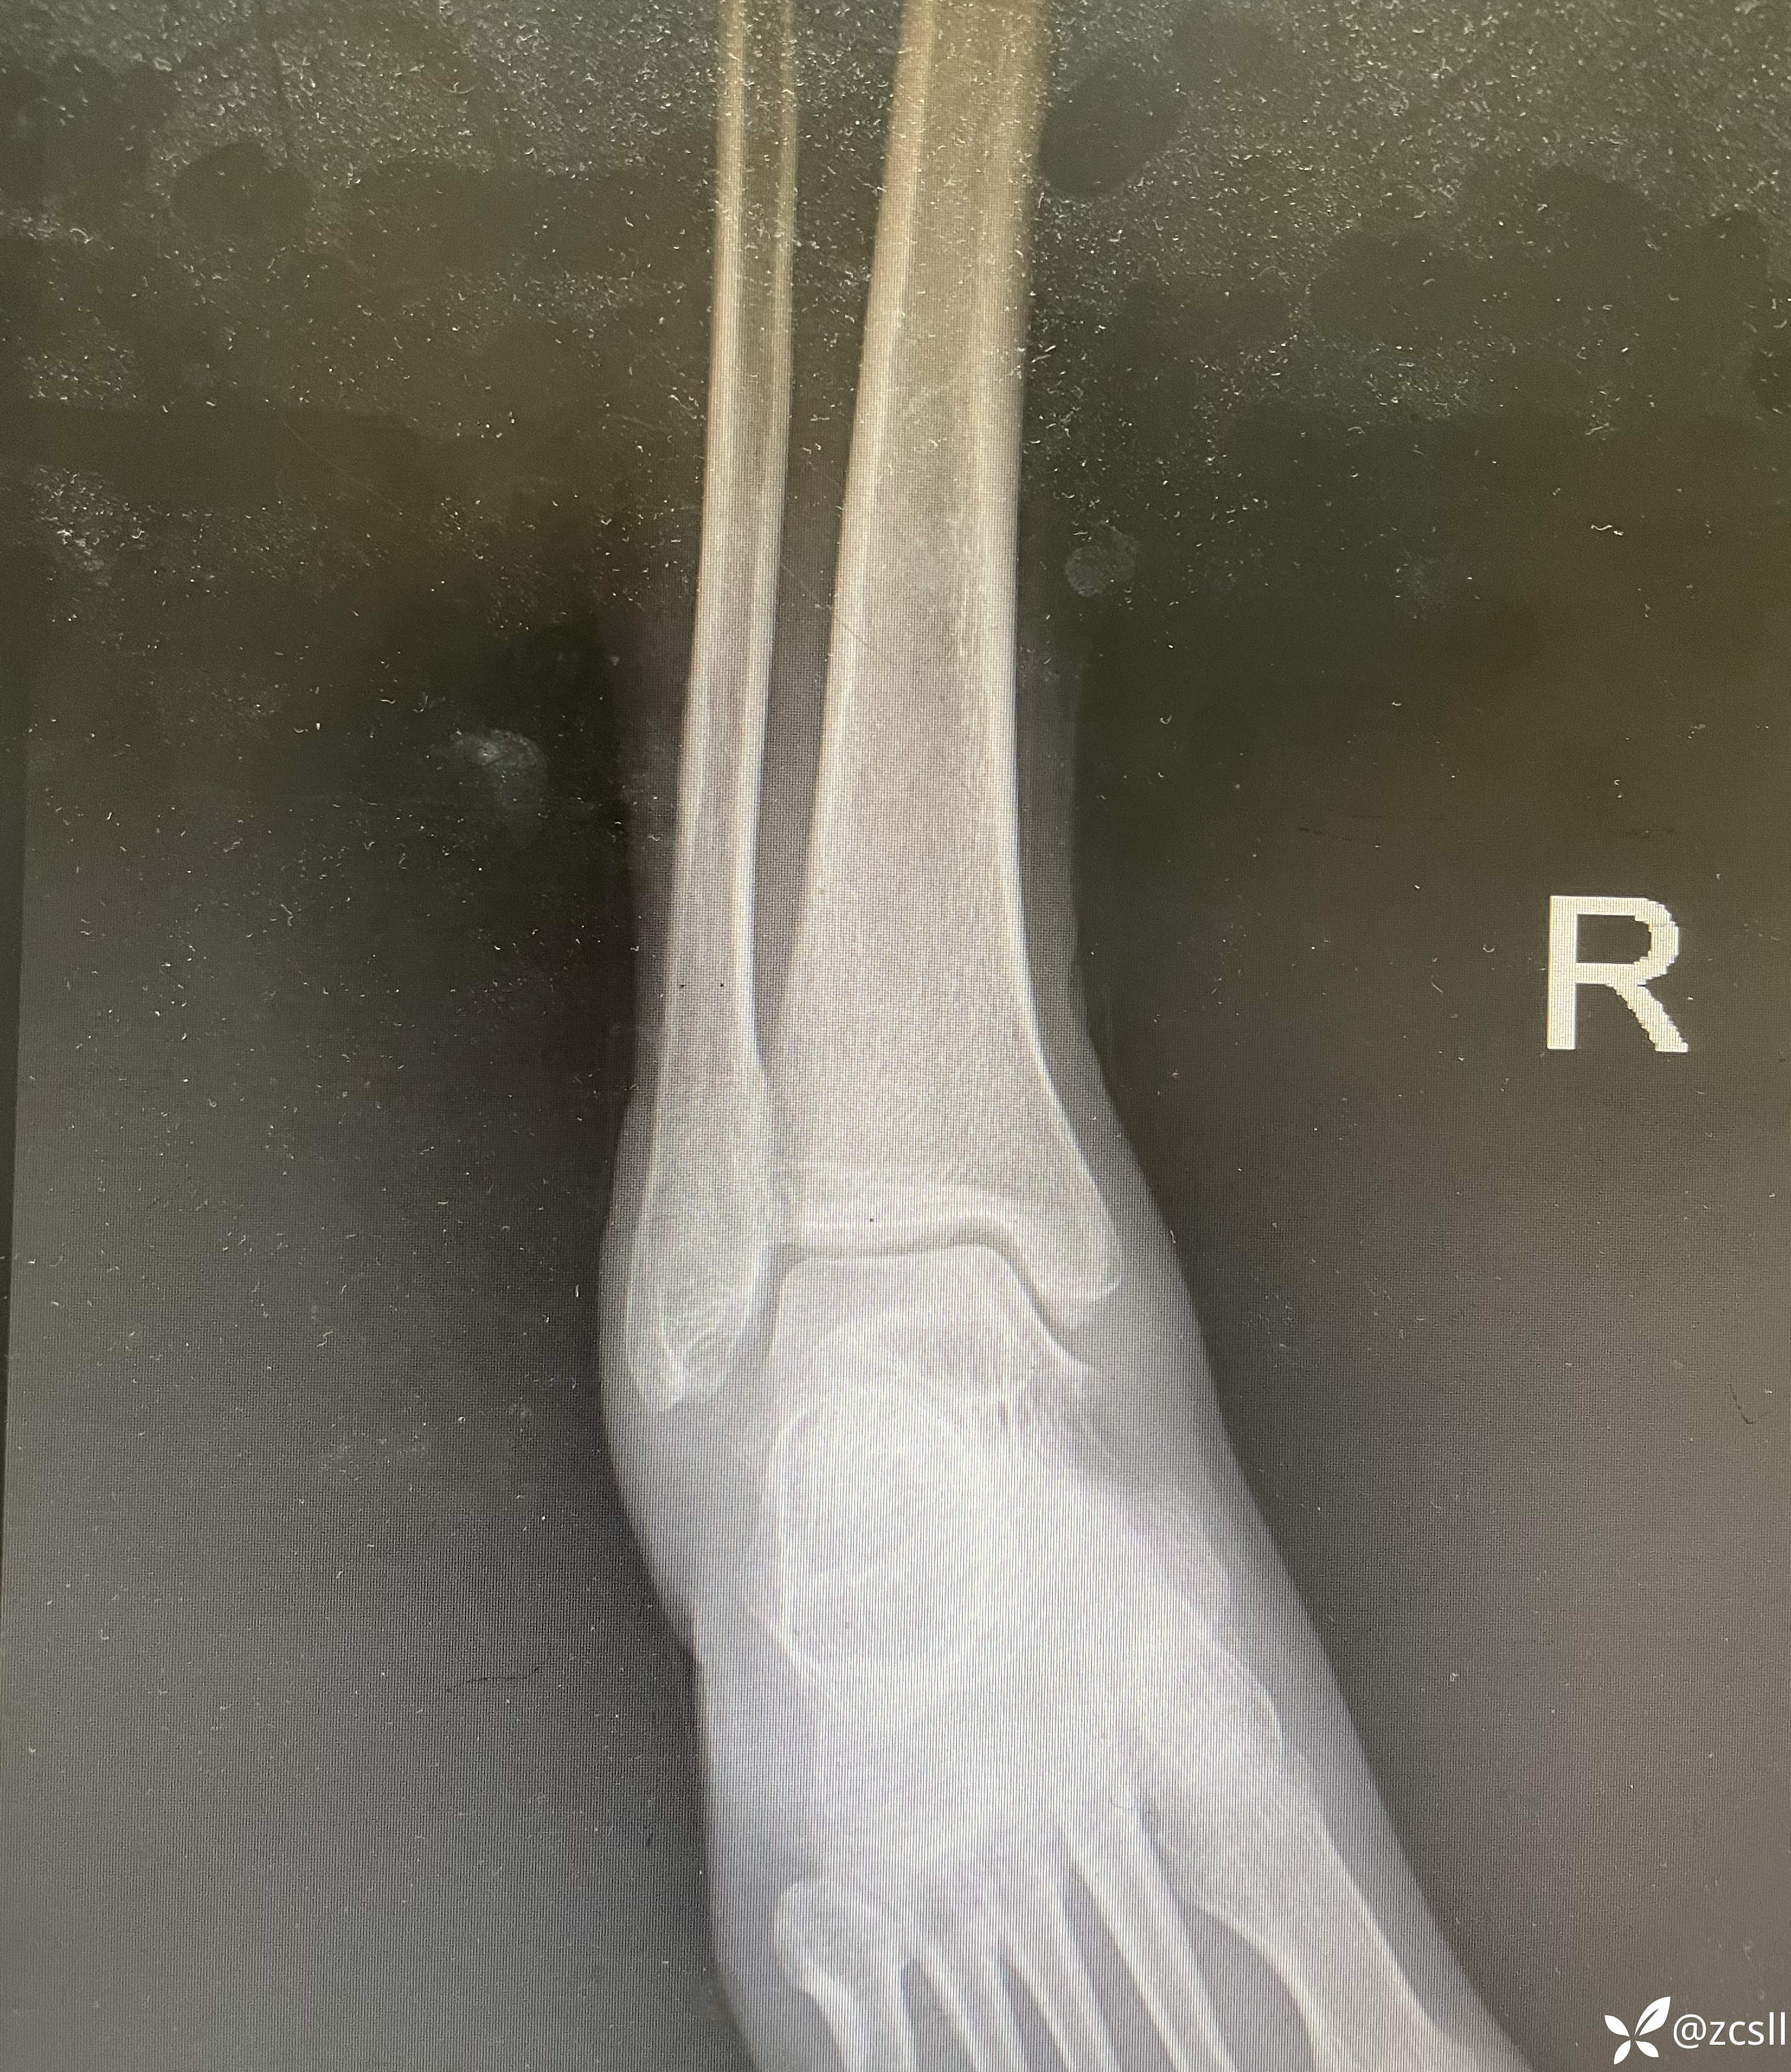

女性,59岁,双踝关节疼痛,局部无红肿,关节彩超提示双轨征,晶体性关节炎不排除。完善踝关节x片提示痛风石?该患者无高尿酸血症病史,入院查血尿酸410。针对这个患者,到底是真痛风还是假痛风呢?期待,路过的同仁能帮助分析分析。